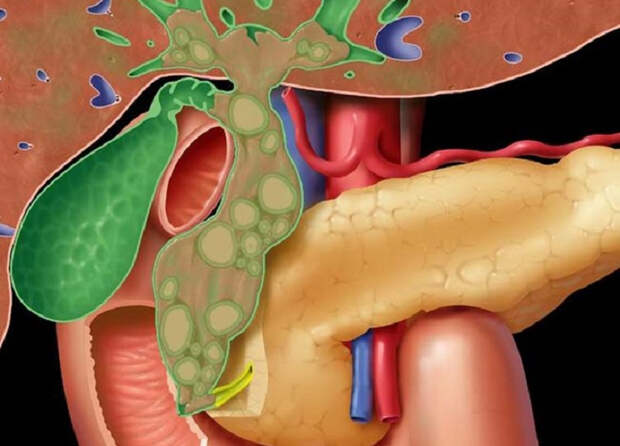

Фотографии и изображения, связанные с симптомами первичного склерозирующего холангита